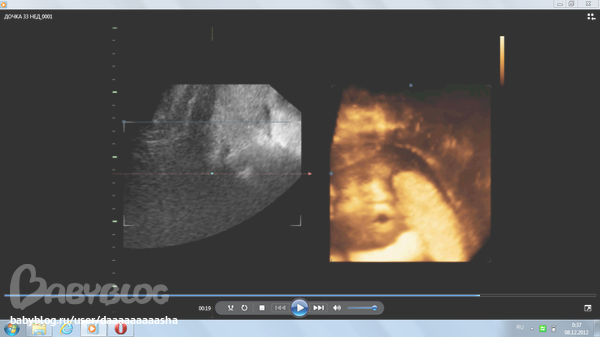

ну и вот пару наших фото... мало что понятно , но по правой стороне видно наш ротик сперва открытый, потом закрытый=))) и ручка трет глазик)